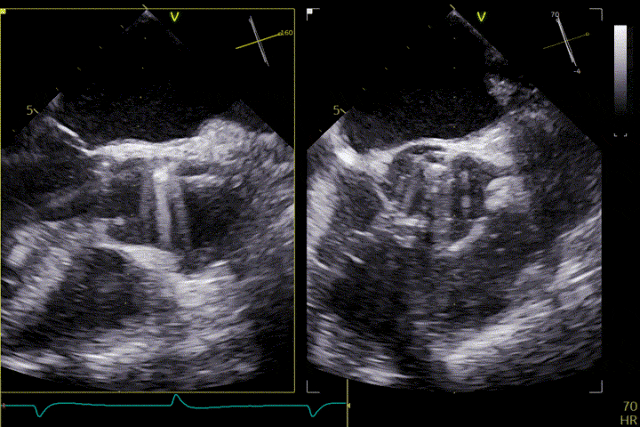

术前超声

术后效果

患者主动脉瓣重度反流纠正,术后无反流、无瓣周漏。术后心脏彩超显示人工生物瓣启闭良好,平均跨瓣压差2mmHg,流速正常。患者恢复情况良好,心功能较术前有了明显改善。